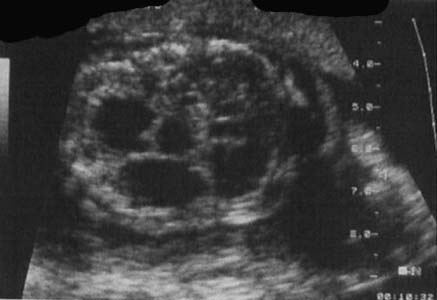

Masse hétérogène (forme macrokystique)